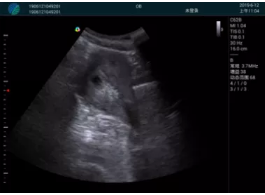

清晰顯示孕囊,通過(guò)軟件包計(jì)算孕齡7w+6d

M20實(shí)時(shí)引導(dǎo),術(shù)中清晰顯示孕囊被破壞和抽吸針的過(guò)程,清晰顯示吸引針

抽吸結(jié)束后縱切子宮,孕囊已被完全抽吸,未見(jiàn)明顯殘留

橫切子宮,發(fā)現(xiàn)右側(cè)宮腔靠近宮角處有少許脫模樣殘留

M20引導(dǎo)下,抽吸針找到右側(cè)宮角處再次清掃

二次抽吸后再次進(jìn)行超聲檢查,宮腔未見(jiàn)殘留,宮腔線(xiàn)清晰顯示